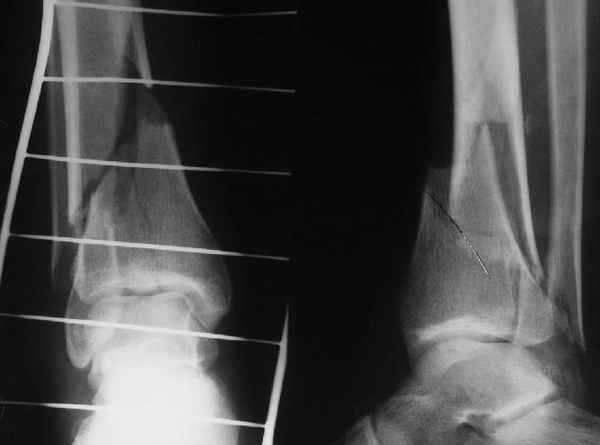

При штифтовании ортопедическим столом не пользуйтесь?